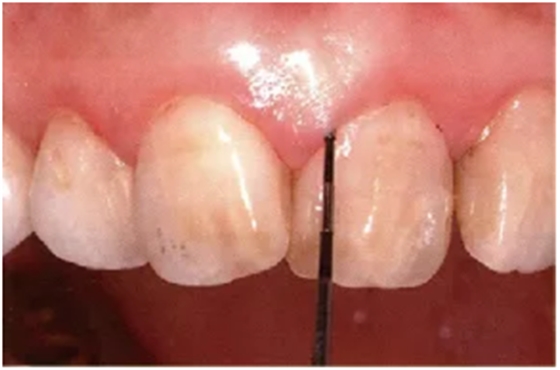

探针要与牙軸平行插入。注意不要探针的尖端离开牙面。

舌侧数值难以读取,要学会利用口镜来读取。

● 颊侧、舌侧探针的插入

通常与牙軸平行插入

舌侧难以看到的位置就利用好口镜来辅助。

注意尽量让探针贴着牙面。